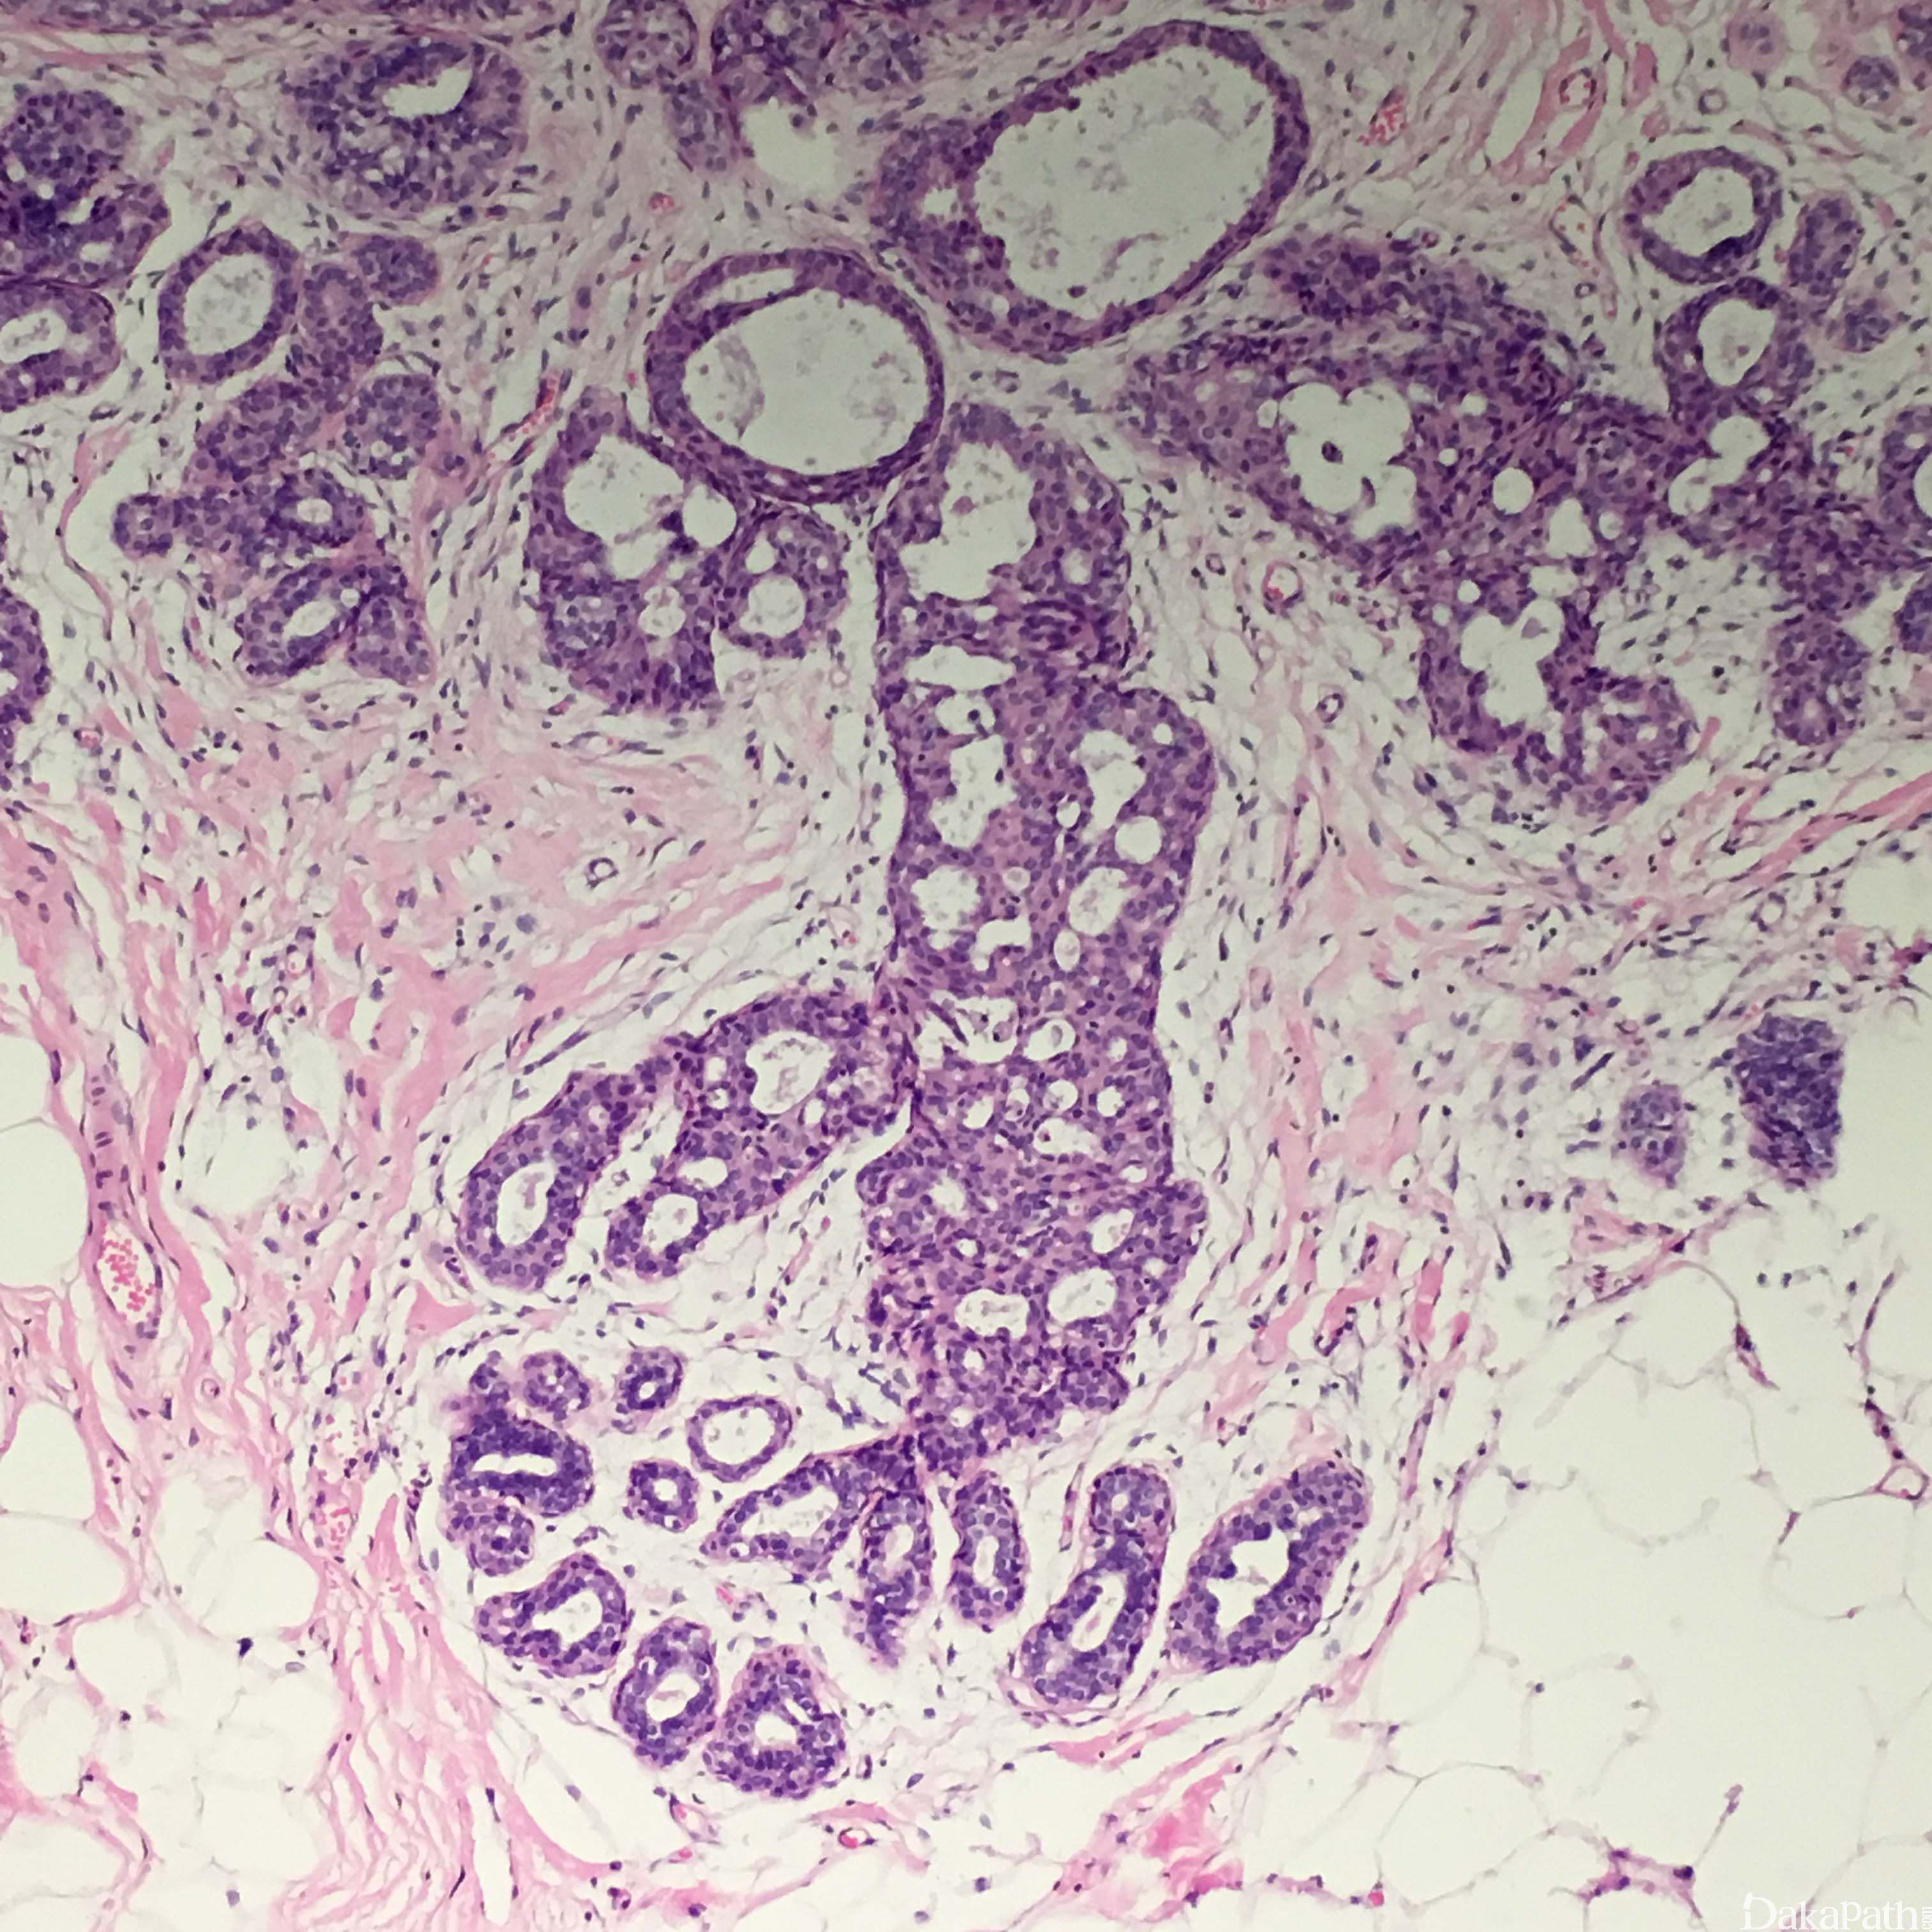

- 组织学结构特征:超过正常的乳腺的两层结构(肌上皮细胞和腺上皮细胞层),细胞杂乱的紧密增生。轻度增生是指 2-4 层增生的腺细胞,旺炽性增生是指大于 4 层增生的腺细胞,可以形成实性的、筛状的或微乳头结构。

- 实性型 UDH 表现细胞大小不等、形状各异,排列杂乱,可以出现导管周围裂隙样的空隙,肌上皮细胞层存在;

- 多孔型 UDH 表现为形成孔的腺腔不规则,腺腔大小和形状各异,经常裂隙样并出现在导管周围,和 ADH 及低级别 DCIS 中看到的圆形的、穿凿样的腺腔不同,不显示围绕腺腔的极向,排列杂乱、可以重叠;有些病例表现为梭形的腺细胞呈明显的流水样或旋涡状排列;

- 微乳头型的 UDH 表现为丛状乳头凸起,基底宽,越往上越细,微乳头之间的上皮也增生,有时微乳头型增生类似在男性乳腺发育和男性乳腺增生中看到的导管上皮增生。